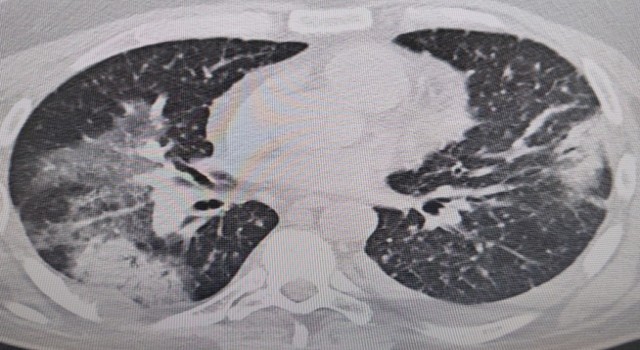

Yazın artan sıcaklıklar dolayısıyla klima kullanımına bağlı olarak ortaya çıkan yaz zatürresi hakkında bilgilendirmelerde bulunan Prof. Dr. Şevket Özkaya, “Klima sularında üreyen ‘Legionella’ bakterisi bu zatürreye sebep olur. O yüzden klima temizliğine önem verilmelidir” dedi.

Bu yazın tüm Türkiye’de sıcak ve nemli olması ve klima kullanımının da artması bekleniyor. Hem ev hem işyerlerinde serinlemek için açılan klimalar ve havalandırmalar yaz aylarında en sık görülen ve halk arasında "zatürre" olarak bilinen pnomoniye neden oluyor. Altınbaş Üniversitesi Tıp Fakültesi, Göğüs Hastalıkları Anabilim Dalı Başkanı Prof. Dr. Şevket Özkaya, kış aylarında grip gibi hastalıklar daha fazla iken yaz aylarında ise bu tip zatürrenin daha sık görüldüğüne dikkat çekti.

Prof. Dr. Şevket Özkaya, “Legionella” bakterisinin klima sularında üremesiyle insanların yaz zatürresine yakalandıklarını ve kış aylarına göre çok daha fazla vakayla karşılaştıkları bilgisini verdi. Klima zatürresinin özellikle kronik rahatsızlığı olanlarda ölümcül olabileceğini belirten Prof. Dr. Şevket Özkaya önemli uyarılarda bulundu. Özkaya, “Klimaların havalandırılmasıyla beraber insanlar ’lejyoner’ bakterilerini akciğerlerine aldığında ’klima pnömonisi’ ya da ’yaz zatürresi’ dediğimiz hastalığa yakalanıyorlar. Bunun özellikle kronik astım, KOAH ve kanser hastalarında ölümcül sonuçlar doğurabileceğini biliyoruz” dedi.